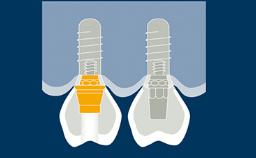

Complete dentures have a longstanding record for rehabilitation of edentulous jaws, but are frequently associated with problems of retention and stability. Patients with these issues may be referred for implant therapy often without first addressing problems of inadequate design and fit of the complete prostheses.

Improving the design and construction of the prostheses may alleviate problems of retention and stability without the need for implants. Therefore, the first step in the rehabilitation of edentulous arches is to establish whether or not the prostheses are adequate.

A complete denture is defined as a removable dental prosthesis that replaces the entire dentition and associated structures of the maxilla or mandible. Complete removable dentures must be designed as ideally as possible.

- discuss the importance of denture base fit and extension for denture retention and support